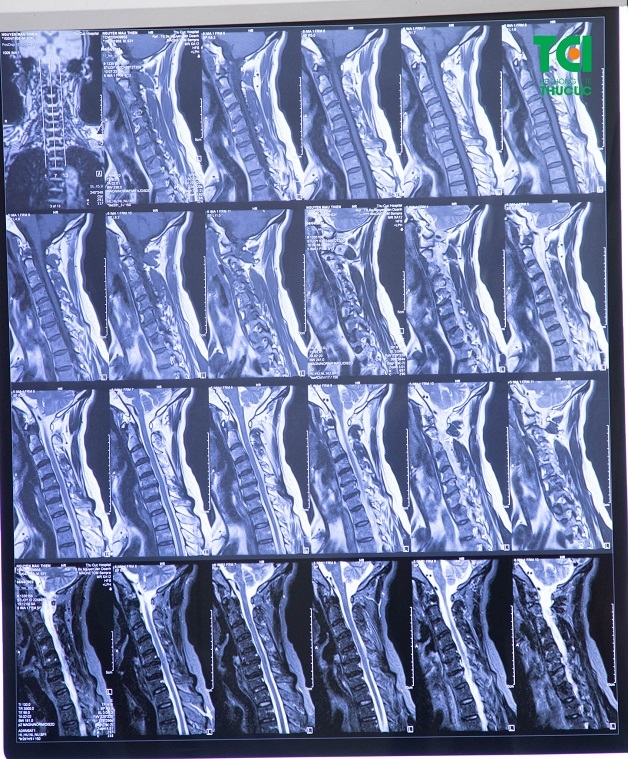

– Chụp cộng hưởng từ (MRI) những hình ảnh được tạo ra từ bằng sóng vô tuyến và từ trường giúp bác sĩ xác định vị trí các dây thần kinh bị chèn ép.

Chụp cộng hưởng từ cột sống cổ không chỉ phản ánh tình trạng tổn thương cột sống (phần cứng) mà còn có thể chẩn đoán tổn thương tủy sống (nằm bên trong ống sống) giúp bác sĩ chẩn đoán chính xác và loại trừ bệnh lý ở tủy sống.